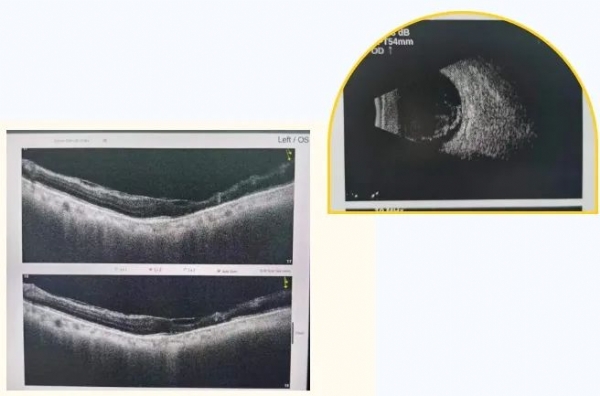

74岁的黄先生,近3年双眼视力持续下降,尤其是2月前右眼视力下降明显。黄先生经过多方打听找到了我院眼科学科带头人王哲,经过王哲详细的专科检查,确诊黄先生为右眼严重玻璃体积血、左眼黄斑前膜和双眼的白内障,需入院先行左眼手术剥离黄斑区的增殖膜,同时停抗凝药物一周后再行右眼玻璃体积血和白内障手术,从而保存和提高患者视力。

由于黄先生长期口服抗凝药,术中剥膜时视网膜极易出血,再加上其左眼黄斑前增殖膜较厚,眼底情况复杂,手术难度较大,合并患有的白内障疾病联合手术增加了患者术后炎症反应。为避免较大的手术创伤,减少手术并发症发生率,更大程度地挽回黄先生的视力,经详细评估后决定给予患者目前最新技术手段解决,即利用20K双刃斜面超高速玻切头进行微创玻璃体切除手术。在“黑科技”超高速手术加持下,黄先生白内障+黄斑前膜的复杂四级手术仅仅用时20分钟就顺利完成,手术过程中黄先生无任何不适。术后第一天,黄先生眼部反应较轻,视力恢复到0.6,他说“就像没做过手术一样”,言语间黄先生的脸上露出了久违的笑容。